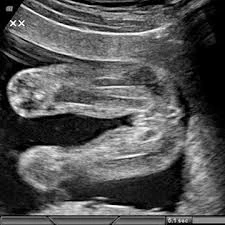

Ayrıntılı Ultrason Rahim plasenta – bebek sistematik gözden geçirilir. Bebek ölçümleri baş boyun, göğüs kafesi kalp karın omurga detaylı İncelenir

Anomali taraması için ayrıntılı ultrason genellikle 18-20. gebelik haftaları arasında gerçekleştirilir. Bu tarama, bebeğin organlarının, sistemlerinin normal gelişimini değerlendirirken, olası anomalileri tespit etmek için yapılan tarama testidir. Uzman doktor ultrason sonucuna dayanarak muhtemel riskleri, önlemleri açıklayabilir.